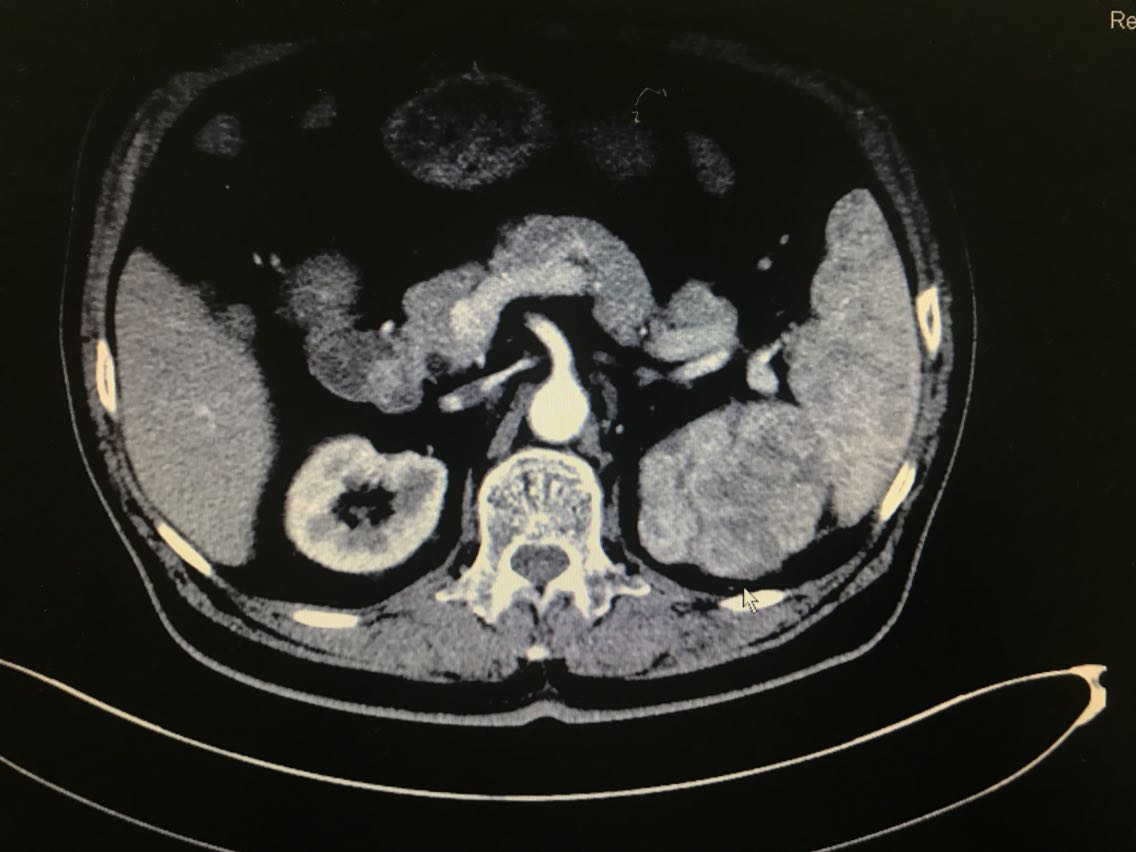

查体无特殊。 辅助检查: 全腹CT示:左肾上极肿块,侵犯左肾上盏并突入左肾盂,性质:左肾细胞癌可能性大,肾盂癌待排,结合临床。

诊断:左肾占位:肾盂癌? 治疗:腹腔镜左肾盂癌根治术

患者左肾占位,肾盂癌、肾癌均有可能,然而两种疾病的手术方式并不一样。前者需要切除同侧输尿管以及部分膀胱,而后者却不需要。那么在诊断不明确的情况下,手术方式以前者为宜。